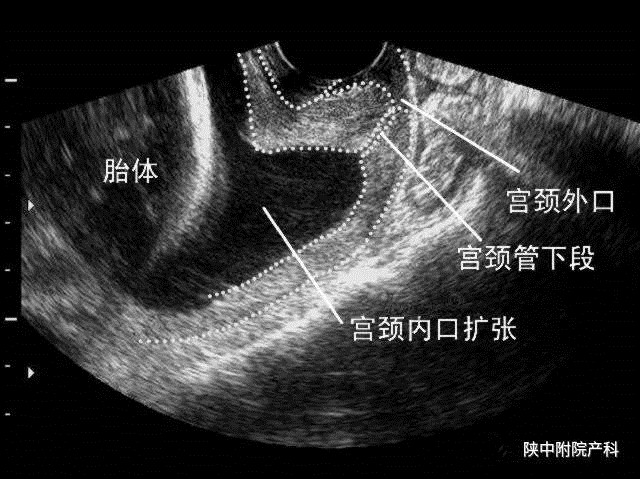

超声检查 经阴道超声目前是较为可靠的诊断方法。正常妊娠14-30周宫颈长度是35-40mm。妊娠头30周宫颈长度是稳定的。在妊娠晚期宫颈进行性缩短,孕产次不影响宫颈长度。几乎所有孕妇,早期妊娠或中期妊娠的早期宫颈长度是正常的。宫颈缩短或漏斗形成常见于18-22周。因此,无论是否有过典型病史,宫颈长度开始测量的时间应该是14-16周,而宫颈长度的临界值定于25mm。怀疑有宫颈机能不全的孕妇,可于14-16周开始,间隔2周连续监测宫颈的变化情况。经腹部超声因膀胱充盈可能使子宫颈拉长以及胎儿对宫颈显示的阻挡,其诊断准确性不如经阴超声。经会阴超声因探头远离宫颈,其准确性也差。